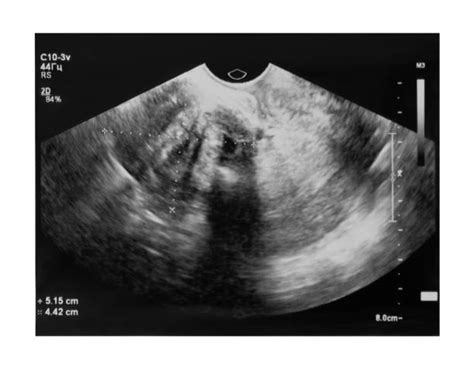

Pri ultrazvukovom (USG) vyšetrení sa hemangióm pečene zobrazí ako homogénne hyperechogénne ložisko, ktoré je ostro ohraničené od okolitého tkaniva a nemá echotieň. V CT obraze je lézia natívne hypodenzná. V arteriálnej fáze sa vysycuje len lobulárna periféria, zatiaľ čo vo venóznej fáze sa vysycuje smerom k centru, čo je známe ako centripetálne plnenie alebo "fenomén dúhovky". Pri neskorších skenoch lézia splýva s okolitým parenchýmom.

tags: #strombotizovany #hemangiom #v #peceni